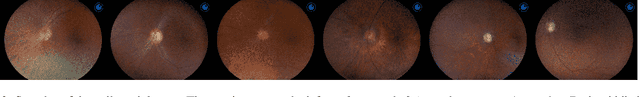

Abstract:Glaucoma is a progressive optic neuropathy characterized by structural damage to the optic nerve head and functional changes in the visual field. Detecting glaucoma early is crucial to preventing loss of eyesight. However, medical datasets often suffer from class imbalances, making detection more difficult for deep-learning algorithms. We use a generative-based framework to enhance glaucoma diagnosis, specifically addressing class imbalance through synthetic data generation. In addition, we collected the largest national dataset for glaucoma detection to support our study. The imbalance between normal and glaucomatous cases leads to performance degradation of classifier models. By combining our proposed framework leveraging diffusion models with a pretraining approach, we created a more robust classifier training process. This training process results in a better-performing classifier. The proposed approach shows promising results in improving the harmonic mean (sensitivity and specificity) and AUC for the roc for the glaucoma classifier. We report an improvement in the harmonic mean metric from 89.09% to 92.59% on the test set of our national dataset. We examine our method against other methods to overcome imbalance through extensive experiments. We report similar improvements on the AIROGS dataset. This study highlights that diffusion-based generation can be of great importance in tackling class imbalances in medical datasets to improve diagnostic performance.